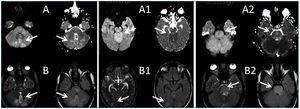

A 26-year-old man presented with a few weeks history of nausea, malaise, blurred vision, a brief episode of visual loss and hypertension. While working, he experienced loss of sight but regained it after a couple of minutes. He had no history of chronical disease. Family history of patient was not contributory-without a family history of vascular disease or hypertension. He was not taking any medications and denied any heavy alcohol, cocaine or intravenous drugs use, but had a 10-pack-year tobacco history. On review of systems, he reported 6-7 kilograms of unintentional weight loss in the past one year. Blood pressure was 150/70mm/Hg, a temperature of 36.8oC, heart rate of 64/min, and respiratory rate of 16/min. Cardiovascular and respiratory system examination was not remarkable. Indirect ophthalmoscopy was performed; retinal detachment (exudative) in both eyes, raised papilla limits, retinal vessel tortuosity, choroidal hypopigmented lesions under retina and superficial haemorrhages were detected. Exudative retinal findings defined as Vogt-Koyanagi-Harada syndrome. Laboratory and ultrasonographic findings were shown at Table 1. Peripheral blood smear revealed; enough platelets with normal morphology, schistocytes were rare, reticulocytes <2%, normochromic normocytic red blood cells. Primary hematological disease was not considered. He was started to be investigated for primary hyperaldosteronism, Cushing's disease and pheochromocytoma. During the follow up in nephrology service, the patient had presyncope, convulsion, hypertensive emergency and altered mental function. His blood pressure was 220/110mm/Hg. Blood pressure was controlled via sodium nitroprusside infusion for 48 hours and amlodipine 10mg, nebivolol 5mg, doxazosin mesylate 8mg at following days in intensive care unit. After the neurology consultation was performed the patient was evaluated with magnetic resonance imaging (MRI). Bulbus, pons and left mesencephalon, basal ganglia, peri-supraventricular white matter areas of increased T2 signal is considered to be consistent with vasogenic edema. Subretinal haemorrhages were detected at posterior parts of both orbit. It was reported as posterior reversible encephalopathy syndrome (Figure 1). After 5 days of intensive care follow up the patient had normal blood pressure. After excluding frequently seen secondary hypertension causes, renal and mesenteric angiography was performed at the same time suspecting renovascular hypertension. Angiography revealed multiple microaneurysms involving the parenchymal branches of the celiac artery, bilateral renal artery and superior mesenteric artery (Figure 2 and Figure 3). After the angiography, eventually, ultrasound-guided renal biopsy was performed. Light microscopy revealed 9 glomeruli with no specific patterns except a slight increase in mesangial matrix. Normal interstisium, tubular focal atrophy and intimal-medial thickening of blood vessels was apparent. Due to increased cellularity obstruction and perivascular fibrosis were found in blood vessels. Histochemically, periodic acid-Schiff, M. Silver, Masson’s Trichrome staining was used. Congo red staining was negative. With direct immunofluorescence method, there was no specific deposition of IgA, IgG, IgM, C3, C4, C1q, fibrinogen, kappa and lambda. Histological diagnosis was reported as signs of vascular myointimal hyperplasia (Figure 4). With all these findings (clinical characteristics such as severe hypertension and renal insuficiency, constitutional symptoms such as malaise and weight loss, inflammatory parameters like elevated erythrocyte sedimentation rate-ESR and C-reactive protein-CRP, angiographic findings) the patient was diagnosed as PAN. Oral prednisolone therapy as 0.5mg/kg/day had been given. But as creatinine levels raised up and hypertension could not be well controlled with drug therapies, eventually hemodialysis was started (Figure 5).

Malignant HT is defined as severe hypertension in association with retinal hemorrhages and/or exudates with or without papilloedema. Hypertensive encephalopathy has been described in the literature as a presenting feature of PAN.16,17 Central nervous system (CNS) signs/symptoms develop in about 20 to 45% of patients, typically in the form of cerebral infarction, which may cause hemiplegia and disturbance of consciousness.18 The most common reported CNS manifestation is diffuse encephalopathy, followed in frequency by focal deficits and seizures.19 Posterior reversible encephalopathy syndrome (PRES) is a clinical entity characterized with headache, nausea, vomiting, seizures, consciousness disturbance, and frequently visual disorders associated with neuroradiological findings, predominantly white matter abnormalities of the parieto-occipital lobes. PAN-associated PRES has been rarely reported.20 Stanzani et al. reported a case of a female patient affected by PAN, presenting with seizures, during an acute hypertensive state and MRI imaging showed increased T2 and FLAIR signal in posterior regions. Papanikolaou reported a case of a female patient with acute renal failure due to PAN. The authors stated that the patient’s clinical course was complicated by an unusual form of hypertensive encephalopathy (as reversible posterior leukoencephalopathy syndrome: RPLS) and cardiogenic shock.21

Here, we report a case of a male patient with PRES in PAN with the involvement of parietal and occipital cortical areas during an acute hypertensive state. The differential diagnosis indicated malignant arterial hypertension with severe retinopathy, hypertensive encephalopathy and renal insufficiency which contained sclerodermal renal crisis, hemolytic uremic sydrome, polyarteritis and systemic fibromuscular dysplasia. Since, PRES was reported as the most common brain imaging abnormality in severe manifestations of thrombotic thrombocytopenic purpura, TTP might also be considered in the differential diagnosis. A hemolytic-uremic syndrome (HUS) can sometimes be presented with malignant hypertension.22 However, the absence of microangiopathic hemolytic anemia and the renal histology prompted us to exclude HUS. The absence of sclerodermal cutaneous lesions disagrees this hypothesis, but it can’t be completely overlooked since the renal involvement may be incipient. Neverthless, in this patient such a diagnosis is less likely on account of his gender, the seronegative immunological tests and the absence of distinctive renal histological signs such as marked adventitial fibrosis, arterial and arteriolar lesions. Also, normal renal doppler ultrasonography and the values for plasma renin activity excluded the presence of renovascular HT.

PRES is a specific form of hypertensive encephalopathy that can be associated with vasculitis and is characterized by transient clinical and neuroradiological findings mainly located in the parietal-occipital areas.27

Figure 1.